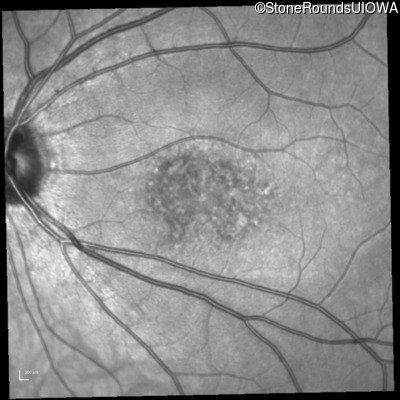

Blue Autofluorescence - Right - 20/32

Exemplar

Blue Autofluorescence - Left - 20/50